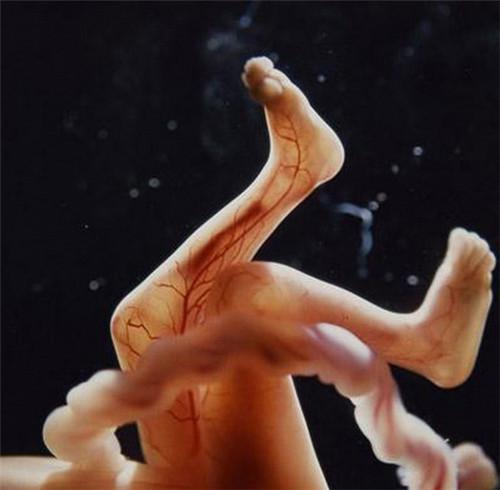

透过薄薄的皮肤,血管清晰可见.

6813337555.jpg